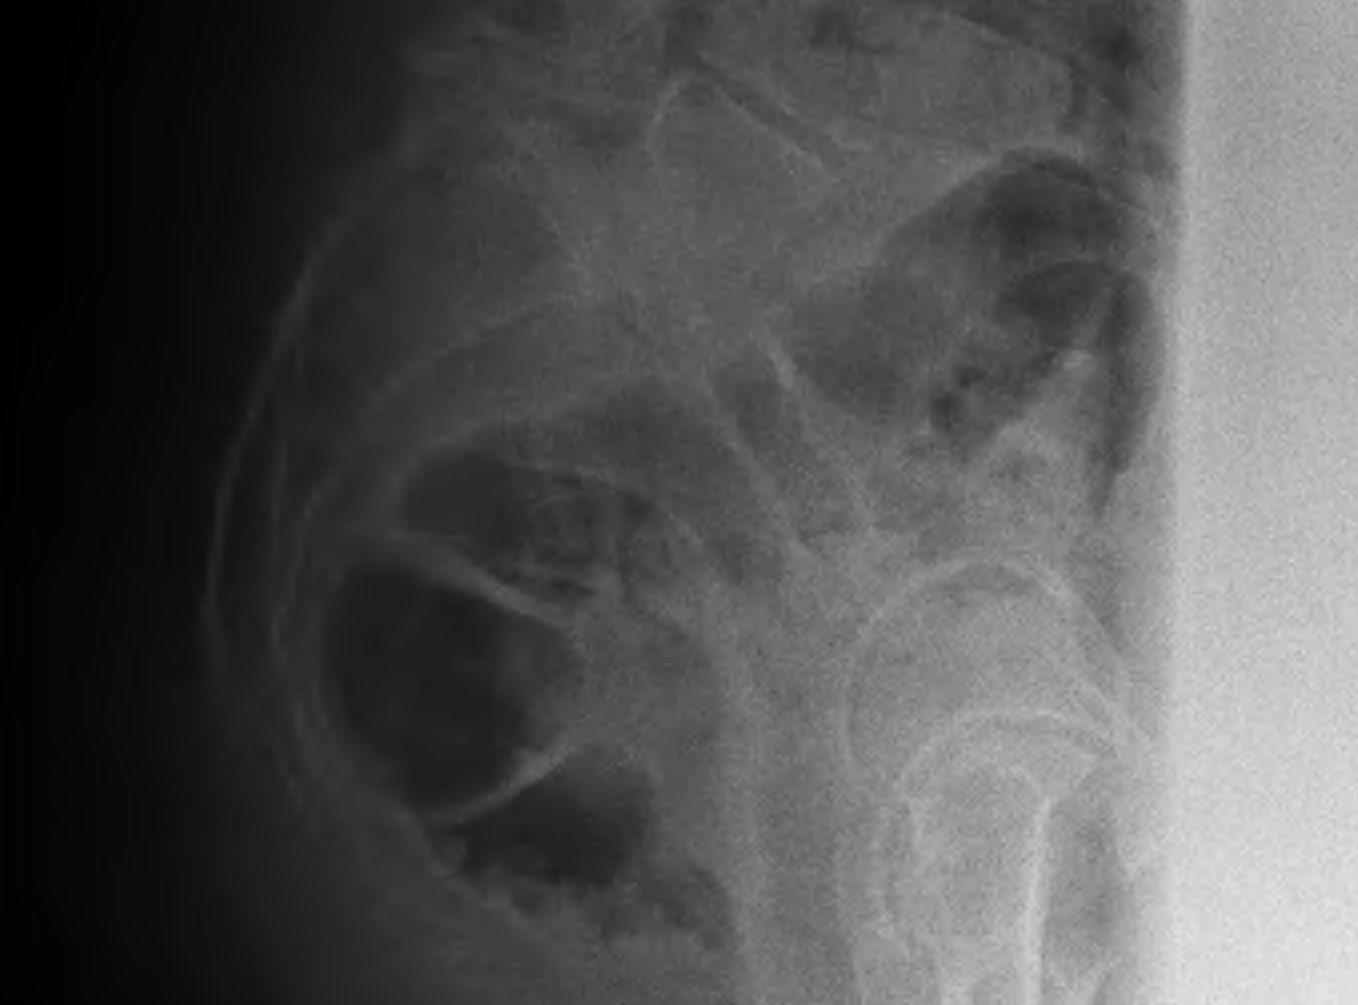

Meyerding Classification

Degree of slip compared with width of S1

- Grade I 0-25%

- Grade II 25-50%

- Grade III 50-75%

- Grade IV 75-100%

- Grade V > 100% / Spondyloptosis

Stability

- stable / slip < 50%

- unstable / slip > 50%